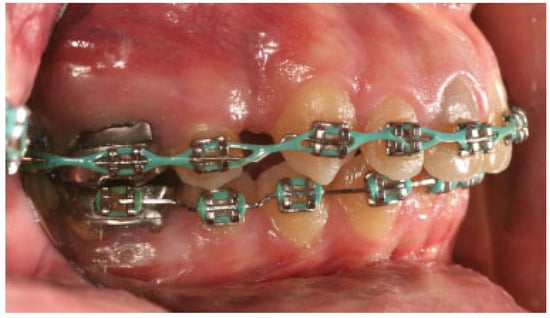

:Case Report